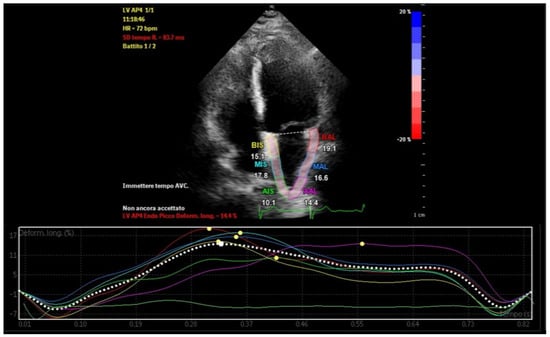

Left atrial strain, measured using speckle-tracking echocardiography, has emerged as a valuable tool for non-invasive assessment of atrial function. This technique evaluates myocardial deformation, dividing the imaging results into three phases: reservoir strain, conduit strain, and booster strain (Figure 1) [8]. Strain imaging enables early detection of atrial dysfunction before structural abnormalities become apparent, facilitating timely intervention and risk stratification [9]. This review examines the interplay between LA-EAT and atrial remodeling, emphasizing the clinical utility of atrial strain analysis in screening, management, and prognosis.

Figure 1.

Phases of left atrial strain in a healthy subject.